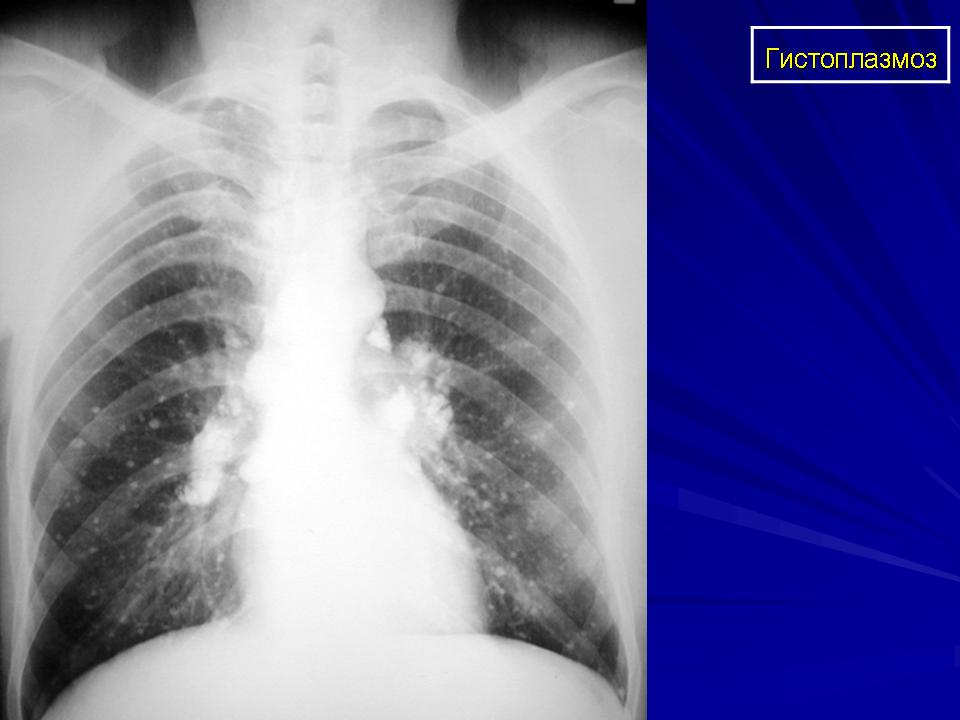

Рентгенологически выявляют крупно- и среднеочаговые тени в виде "ватных хлопьев", которые могут сливаться. В дальнейшем инфильтраты полностью исчезают или на их месте образуются очаги фиброза и кальцинации.

Острая форма диссеминированного гистоплазмоза проявляется высокой лихорадкой гектического или неправильного типа, повторными ознобами и потоотделением, выраженными симптомами общей интоксикации (головная боль, мышечные и суставные боли, тошнота, рвота, боли в животе, нарастающая слабость). На этом фоне появляются множественные вторичные очаги как результат диссеминации: различного рода экзантемы (макулопапулезная, фурункулоподобная, геморрагическая, типа многоформной или узловатой эритемы), лимфаденопатия, мезаденит, увеличение печени и селезенки, энцефалит или менингоэнцефалит, септический эндокардит, язвенный колит, перитонит. Клинические и рентгенологические изменения могут напоминать милиарный туберкулез (при аэрогенном инфицировании).

Клиника. Гистоплазмоз легких протекает как острое или хроническое, эпидемическое заболевание. Инкубационный период— 1-2 нед. Атипическая пневмония сопровождается увеличением лимфатических узлов, гектической лихорадкой. В крови — нейтрофильный лейкоцитоз, моноцитоз, анемия, увеличенная СОЭ. Рентгенологически — хлопьевидные тени, усиление корней легких. При повторной инфекции развивается хронический полостной гистоплазмоз, сходный с туберкулезом. Возможна диффузная интерстициальная пневмония с исходом в милиарную кальцификацию легких. Может сформироваться округлый инфильтрат — гистоплазмома. Медиастинальная форма протекает с увеличением медиастинальных лимфатических узлов, ведущим к стенозированию бронхов, трахеи, пищевода. Продолжительность заболевания — до 8-12 мес. Наибольшая смертность наблюдается в первые 6 нед. Хронический диссеминированный гистоплазмоз наблюдается у ослабленных больных туберкулезом, опухолями, лейкозом.